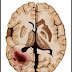

Penyebab Kanker Otak dan Gejalanya

Tumor otak mungkin ganas (kanker) atau non-ganas (jinak). Mereka menghasilkan dari pertumbuhan tidak normal dari jaringan otak.

Karena otak terletak dalam kandang kurus kuat tengkorak, pertumbuhan atau tumor yang terjadi dalam jaringan ini dapat membuat tekanan pada jaringan otak sensitif. Hal ini menyebabkan gangguan dari berbagai fungsi otak dan saraf yang termasuk masalah dalam visi, pidato, keseimbangan dll.